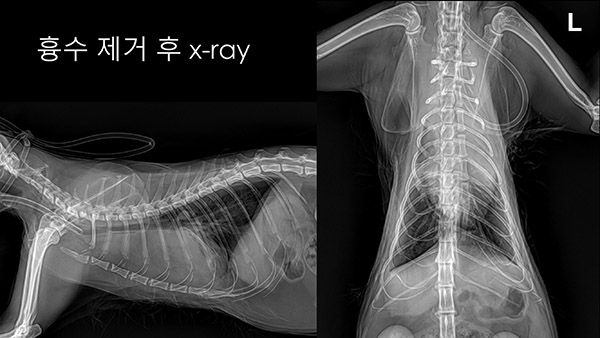

CT검사 결과 전 종격동에 조영 증강된 mass가 보이고, 이 mass로 인해 cyst가 형성된 것을 확인할 수 있었습니다[그림4]. 흉수는 250ml 천자하였고, exudate 양상으로 나왔습니다[그림5]. 흉수 천자 후 방사선 사진은 다음과 같습니다[그림6].